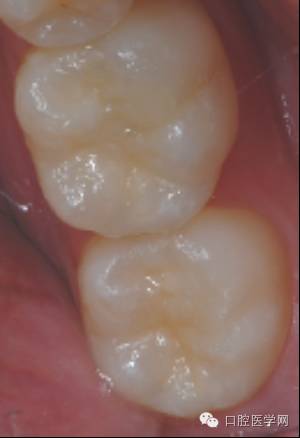

印章覆盖成形

要点:

1、若龋洞较深,分层充填,在最后的一层树脂固化前覆盖印章

2、 若龋洞较浅,可单层充填

3 、树脂不宜过多,否则影响形态恢复的准确性,并为调牙合带来困难,影响充填效果

初步完成

检查咬合